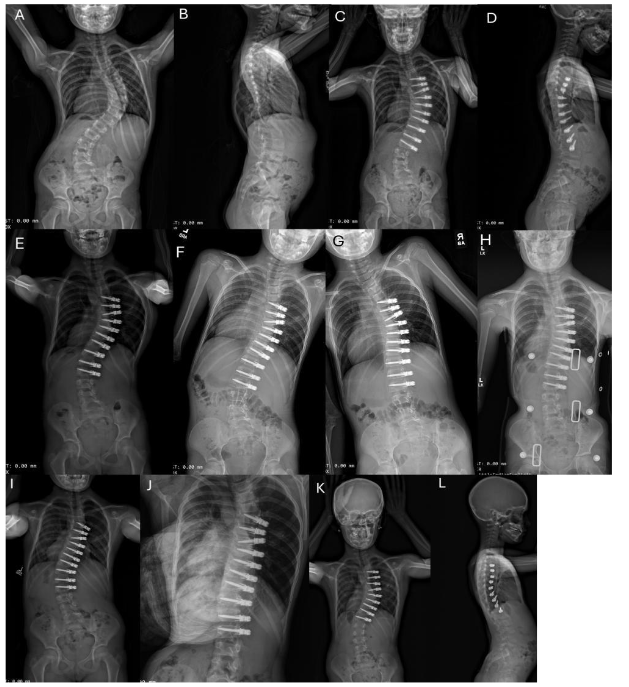

We present a cohort of 15 patients (17 curves) with early onset scoliosis. The mean follow-up was 48.3 months (range 25 to 86 months). In terms of the surgical construct, 9 patients (53%) received a simple line construct, while the remaining 8 patients (47%) were treated with a dual line construct. The placement of one or two screws per vertebra was a subjective determination by surgeon MDA depending on the size of the patient’s vertebrae.

4.0 Revision and Subsequent Stage Surgery

Six of 15 patients (40%) required a subsequent stage ASC for additional curve correction. The other two patients (13%) required spinal fusion. One patient with a stiff curve measuring 106° had a fusion for persistent crankshaft. The instrumented curve corrected to 36°, but the curve crankshafted below the L2 instrumentation necessitating a fusion 3.5 years after initial ASC surgery.

There is a trend that the 11 patients who required second surgeries had fewer intervertebral de-tethering releases compared to the 4 patients who underwent ASC without subsequent surgeries. The average age of the patients undergoing ASC was 8 years old. It is expected that the curve will continue to grow and the spinal column to function correctly.